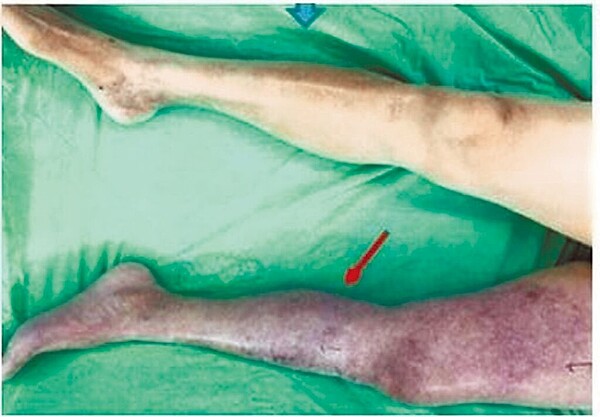

李明義說明,下肢水腫與靜脈栓塞雖都會導致下肢腫脹疼痛,有時候會造成民眾誤判,但深部經脈栓塞在膚色上會較暗沈,也會有紫斑的變化,若要了解自己是否為深部靜脈栓塞,仍需要就醫透過抽血檢測栓塞指數才能辨識。

放射科醫師黃培毓則表示,通常下肢深部靜脈栓塞形成時並無症狀,後期會有患側下肢腫脹疼痛、發熱等症狀;小腿肚也會在足背彎曲時疼痛,稱霍曼氏徵象,若有相關症狀,建議接受下肢血管電腦斷層或超音波檢查,以鑑別肌肉筋膜問題或蜂窩性組織炎,並積極接受治療。